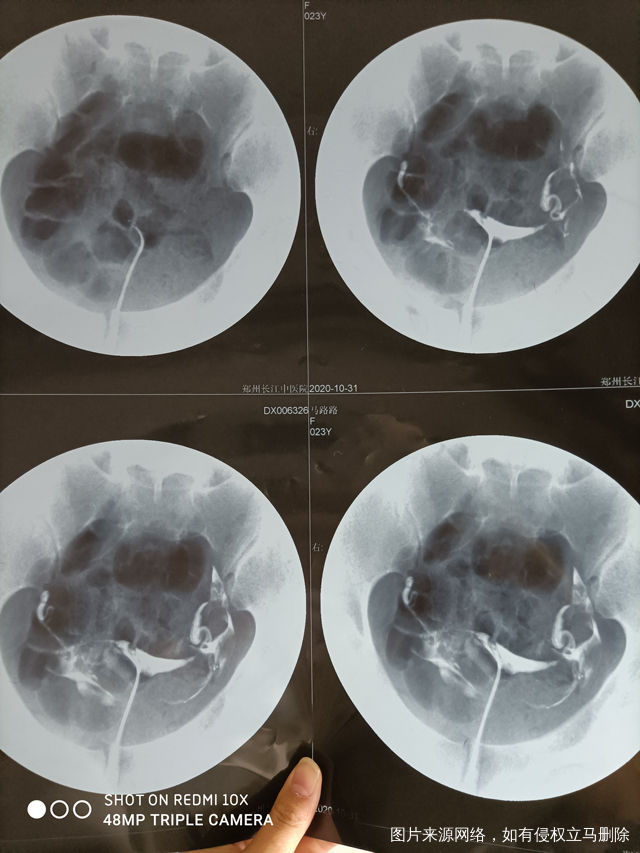

做完输卵管造影第六天了小腹还是感觉沉甸甸的如

可以热敷腹部,如果有发热,腹痛加剧,白带量多,有异味,随时就医

刘翠荣

5位已回答